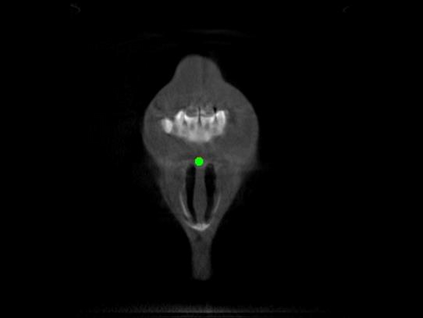

Detecting 3D landmarks on cone-beam computed tomography (CBCT) is crucial to assessing and quantifying the anatomical abnormalities in 3D cephalometric analysis. However, the current methods are time-consuming and suffer from large biases in landmark localization, leading to unreliable diagnosis results. In this work, we propose a novel Structure-Aware Long Short-Term Memory framework (SA-LSTM) for efficient and accurate 3D landmark detection. To reduce the computational burden, SA-LSTM is designed in two stages. It first locates the coarse landmarks via heatmap regression on a down-sampled CBCT volume and then progressively refines landmarks by attentive offset regression using multi-resolution cropped patches. To boost accuracy, SA-LSTM captures global-local dependence among the cropping patches via self-attention. Specifically, a novel graph attention module implicitly encodes the landmark's global structure to rationalize the predicted position. Moreover, a novel attention-gated module recursively filters irrelevant local features and maintains high-confident local predictions for aggregating the final result. Experiments conducted on an in-house dataset and a public dataset show that our method outperforms state-of-the-art methods, achieving 1.64 mm and 2.37 mm average errors, respectively. Furthermore, our method is very efficient, taking only 0.5 seconds for inferring the whole CBCT volume of resolution 768$\times$768$\times$576.